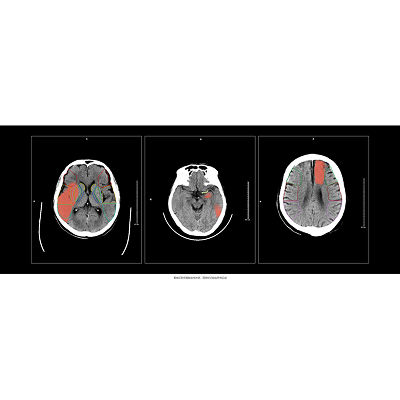

某三甲医院,一女性患者因突发左侧肢体无力、失语和双眼凝视等症状入院。

医生基于一站式CT扫描结果以及脑缺血AI分析,诊断该患者存在脑缺血情况,右脑ASPECTS评分为6分,有4个受影响区域。值得注意的是,该患者的豆状核和岛叶区域存在缺血问题,但由于早期征象不易识别,医生借助AI辨别发现出这两处区域的缺血情况。

而结合头颅CTP AI结果,可发现该患者右侧大脑半球异常灌注,CTA也清晰显示出患者右颈内动脉及大脑中动脉闭塞。因此,医生决定采取经皮颅内动脉取栓术。

术后第3天,MRI结果与AI评估结果一致。术后第12天,该患者无新发不适,遂顺利出院。科室医生表示:“Al可以准确检测出像素级的异常,并通过智能评分为我们提供治疗的参考意见。”